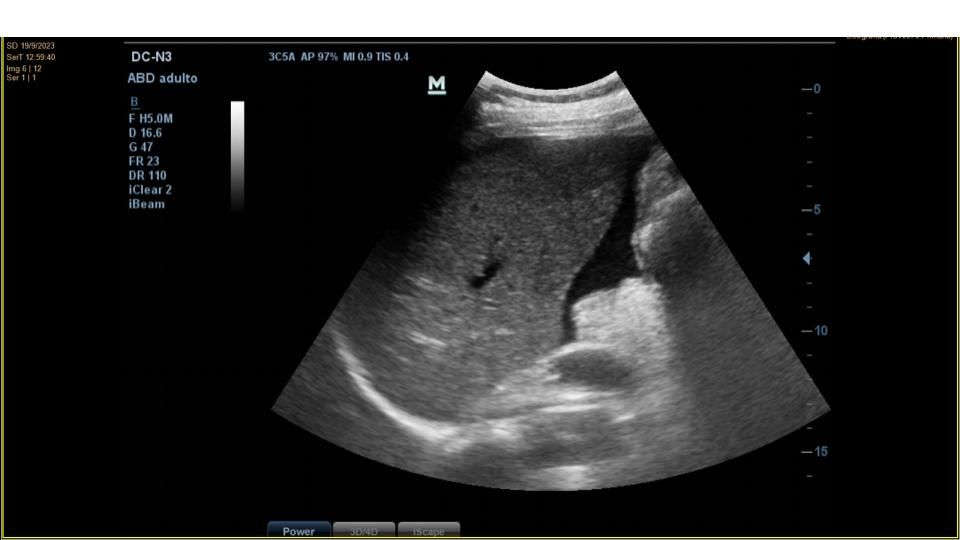

Se realiza ecografía clínica abdominal en el mismo acto para confirmar presencia de líquido y tratar de identificar la ocupación en flanco derecho.

La ecografía confirma la presencia de moderada cantidad de líquido libre abdominal y de una imagen de unos 10 cm de diámetro mayor, anecogénica, tabicada, que parece depender de ovario derecho.